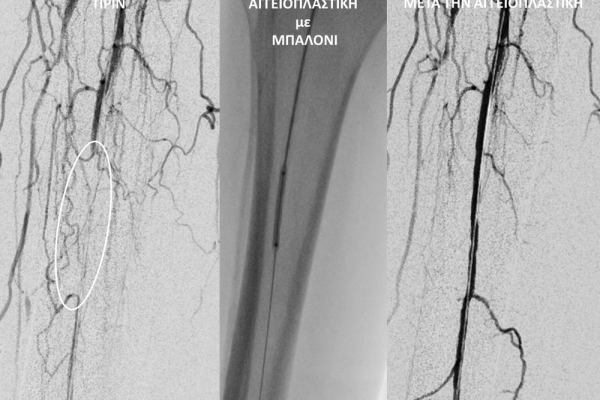

O σακχαρώδης διαβήτης είναι μεταβολική ασθένεια η οποία χαρακτηρίζεται από αύξηση της συγκέντρωσης του σακχάρου στο αίμα (υπεργλυκαιμία) και διαταραχή του μεταβολισμού της γλυκόζης. Ο βαθμός αύξησης της γλυκόζης στο αίμα και η παραμονή των αυξημένων τιμών της για μεγάλο χρονικό διάστημα βλάπτουν, κυρίως, τα μικρά αγγεία, προκαλώντας διαβητική νευροπάθεια, διαβητική νεφροπάθεια, αμφιβληστροειδοπάθεια κ.τ.λ., με σοβαρότατες συνέπειες σε πολλά όργανα-συστήματα.Στην Ελλάδα κάθε χρόνο πραγματοποιούνται 2.000 – 3.000 ακρωτηριασμοί κάτω άκρων, αφού το 4-5% των πασχόντων από διαβήτη εμφανίζει περιφερική αγγειοπάθεια με έλκη ή και γάγγραινα στα πόδια. Σε ποσοστό 80% οι ακρωτηριασμοί θα μπορούσαν να αποφευχθούν και η επεμβατική ακτινολογία μπορεί να βοηθήσει σημαντικά.Η διαδερμική ενδαγγειακή αγγειοπλαστική (percutaneous transluminal angioplasty, PTA) είναι μια ελάχιστα επεμβατική μέθοδος αντιμετώπισης των αρτηριακών στενώσεων ή και αποφράξεων του διαβητικού ποδιού (περιφερικήδιαβητικήαρτηριοπάθεια).